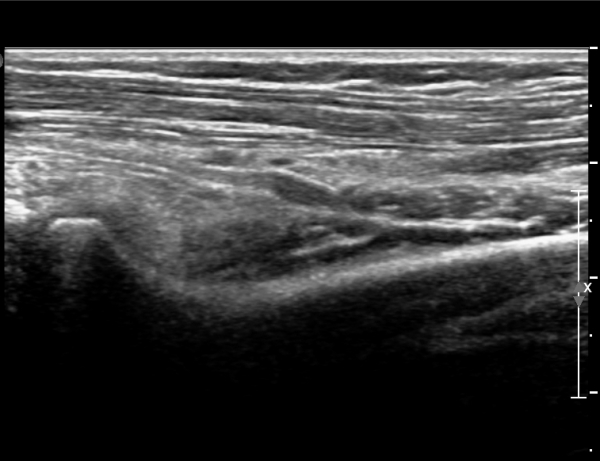

¾Æ·§ÆÈÀ» ȸ³»ÇÑ »óÅ¿¡¼­ Èİñ°£½Å°ßÁ¾´Ü¸é°Ë»ç»ó ȸ¿Ü±Ù ±ÙÀ§ºÎ¿¡¼­ Èİñ°£½Å°æÀÇ Àú¿¡ÄÚ

ºÎÁ¾ÀÌ °üÂûµÈ´Ù(»çÁø 3, 4).